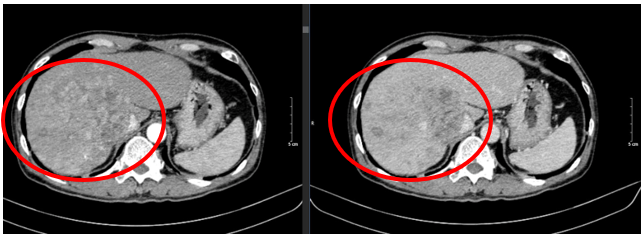

- Chụp cắt lớp vi tính ổ bụng:

Hình 1. Hình ảnh khối nốt nhu mô gan hai bên lan tỏa(vòng tròn đỏ) - tính chất HCC, xâm lấn gây huyết khối các nhánh phải và thân chung tĩnh mạch cửa

Hình 4. So sánh kích thước và hình thái khối u trước điều trị (vòng tròn đỏ) và sau điều trị 3 tháng (mũi tên vàng).

Bệnh nhân đạt đáp ứng tốt với điều trị: khối u thu nhỏ kích thước đáng kể, lâm sàng được cải thiện rõ rệt. Trong quá trình điều trị,bệnh nhân có xuất hiện một số tác dụng phụ như: mệt mỏi, hội chứng bàn tay bàn chân mức độ nhẹ. Ngoài ra bệnh nhân không gặp tác dụng phụ khác.

Đánh giá theo tiêu chuẩn mRECIST 1.1, bệnh đáp ứng một phần (PR – Partial Responce). Hiện tại, bệnh nhân tiếp tục được điều trị với lenvatinib liều 8mg/ngày.